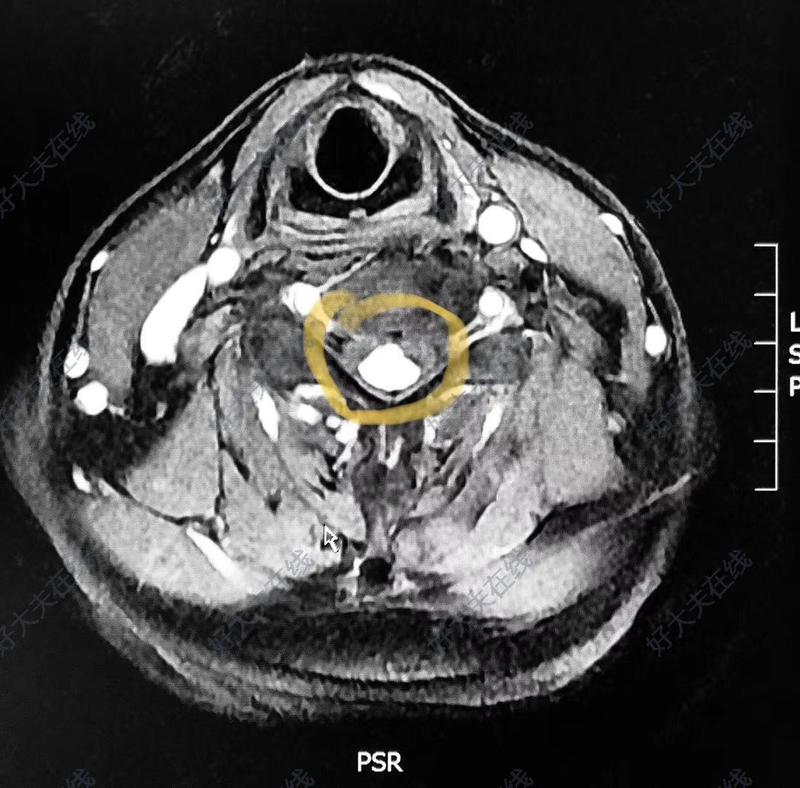

如果說哪一種脊髓腫瘤手術(shù)最富挑戰(zhàn)性,那無疑是血管母細(xì)胞瘤。因為它血供極其豐富,術(shù)前如果診斷不明確,術(shù)中按照常規(guī)腫瘤行分塊切除,將導(dǎo)致不可控制的大出血,造成災(zāi)難性的后果,因而被稱作最兇險的椎管內(nèi)腫瘤。血管母細(xì)胞瘤是一種少見的髓內(nèi)腫瘤,約占髓內(nèi)腫瘤的2%~15%,占整個椎管內(nèi)腫瘤的1%~5%。血管母細(xì)胞瘤的確切病因并不清楚,只知道它是來源于脊髓的血管內(nèi)皮細(xì)胞的腫瘤,是一種富血管的良性腫瘤。脊髓血管母細(xì)胞瘤最常見的發(fā)生部位是脊髓頸段和胸段,男性更常見,平均發(fā)病年齡約為34歲。血管母細(xì)胞瘤最常見于髓內(nèi),但少數(shù)可橫跨硬膜內(nèi)-硬膜外,也有極個別為硬膜外型。大部分血管母細(xì)胞瘤為散發(fā)、單發(fā)病例,大約20%-30%的病人有相關(guān)的家族史,稱作家族性血管母細(xì)胞瘤,是VonHippel-Lindau綜合征(VHL),一種常染色體顯性遺傳病的表現(xiàn)之一,這部分患者往往還伴有視網(wǎng)膜血管瘤、內(nèi)臟腫瘤或囊腫、多發(fā)性中樞神經(jīng)系統(tǒng)腫瘤等,這無疑增加了治療的難度。脊髓血管母細(xì)胞瘤大多為實質(zhì)性的,腫瘤有完整的包膜,瘤體呈暗紅色,血供豐富,常常有明顯的供血動脈和曲張的靜脈。部分腫瘤鄰近的脊髓常伴發(fā)空洞或腫瘤直接呈附壁結(jié)節(jié)的囊性。該病與其他髓內(nèi)腫瘤的臨床表現(xiàn)類似,最常見的癥狀是感覺異常、肌力下降和疼痛。常呈緩慢進(jìn)展型,在數(shù)月或數(shù)年內(nèi)癥狀逐漸加重。少數(shù)可因瘤內(nèi)出血或蛛網(wǎng)膜下腔出血癥狀呈現(xiàn)突然加重或急性起病。實性血管母細(xì)胞瘤及粗大的引流靜脈MRI是診斷血管母細(xì)胞瘤最好的手段,可以準(zhǔn)確顯示腫瘤的位置、大小、形態(tài),有無空洞和血管流空影。MRIT2加權(quán)像上可見瘤體內(nèi)、腫瘤邊緣和鄰近區(qū)域不規(guī)則的點狀或線狀血管流空影,增強(qiáng)掃描腫瘤顯著強(qiáng)化,呈極高信號強(qiáng)度,此為血管母細(xì)胞瘤的典型特征。囊性血管母細(xì)胞瘤多呈大囊腔小結(jié)節(jié)型,結(jié)節(jié)在MRI增強(qiáng)掃描時強(qiáng)化明顯而囊壁不強(qiáng)化。MRI鑒別困難時,可利用血管母細(xì)胞瘤富血運(yùn)的特征,借助DSA以協(xié)助確立診斷。另外,不同于其他椎管內(nèi)腫瘤,脊髓血管造影對于血管母細(xì)胞瘤手術(shù)方案的制訂也有重要價值。它可以顯示腫瘤的供血動脈,引流靜脈,能判定供血動脈的數(shù)目、部位、來源和方向,尤其是腫瘤和脊髓動脈的關(guān)系,保障手術(shù)的順利進(jìn)行。脊髓血管母細(xì)胞瘤MRI特征性表現(xiàn)血管母細(xì)胞瘤屬脊髓良性血管瘤,對放射治療不敏感,手術(shù)治療是最有效的根治手段。但因其血運(yùn)特別豐富,且位于髓內(nèi),代償空間狹小,所以手術(shù)難度較高,如操作不當(dāng)則可產(chǎn)生嚴(yán)重后果。切除腫瘤前應(yīng)先暴露阻斷供血動脈,然后沿血管瘤的包膜小心分離四周,以小功率雙極電凝反復(fù)電灼血管瘤包膜,縮小血管瘤體積,最后處理引流靜脈,完整切除血管瘤。切忌分塊切除或先阻斷引流靜脈,否則會引起難以控制的出血,模糊手術(shù)視野,又易損傷正常組織,增加手術(shù)難度。在電凝腫瘤包膜時應(yīng)持續(xù)滴水以降低脊髓溫度,防止熱傳導(dǎo)損傷脊髓。脊髓血管母細(xì)胞瘤手術(shù)示意圖如果腫瘤過大,出血風(fēng)險大,手術(shù)前還可以考慮將腫瘤的部分血供進(jìn)行栓塞,栓塞后腫瘤出血會明顯減少,張力降低,視野清晰,更有利于腫瘤的完整切除。術(shù)中也可通過電生理監(jiān)測,減少脊髓、神經(jīng)損傷;同時,手術(shù)應(yīng)該盡可能減小對脊柱及周圍組織的騷擾,避免可能出現(xiàn)的脊柱不穩(wěn)、疼痛及脊柱活動度受限,進(jìn)而防止脊柱退變性改變??傊?,脊髓血管母細(xì)胞瘤在臨床上雖然相對少見,但診斷上具有一定的特征性,術(shù)前多可作出正確的診斷。雖然病情可能兇險,但在條件允許的情況下,可采用血管內(nèi)栓塞為手術(shù)的實施創(chuàng)造良好的條件。血管母細(xì)胞瘤手術(shù)的難度相對較大,應(yīng)遵循一定的原則,在保護(hù)脊髓功能的前提下整塊切除腫瘤,改善脊髓功能,提高患者預(yù)后。